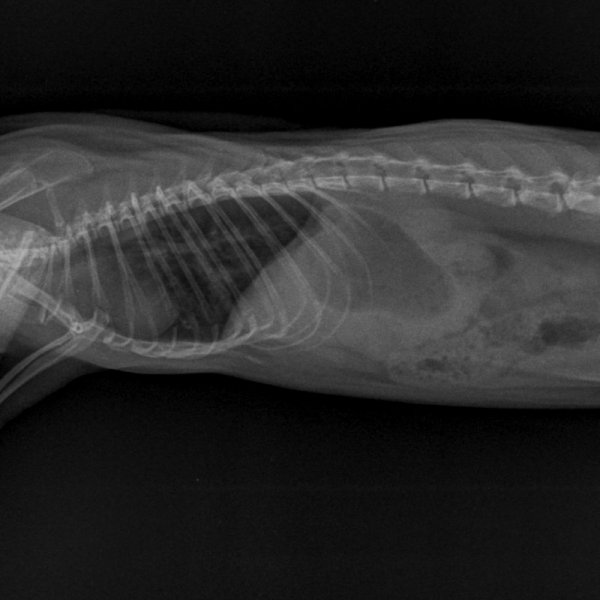

Début avril, comme vu plus tôt, 10 jours de doxycycline, 5mg/kg/12h, en PO pour Koba suite à symptômes respis avec perte de poids.

Il y avait du mieux donc on a arrêté au bout de 10 jours.

Et puis fin avril sa respiration est devenue accélérée de façon flagrante, avec quelques rares bruits respiratoires.

On est repartis sur un mois (28 jours ajd) de doxycycline, toujours à 5mg/kg/12h en PO (bon, pour compenser les risques de perte, on était plus sur du 6mg/kg).

Nouvelle radio ajd. Toujours un peu d'opacité pulmonaire mais le vétérinaire trouve qu'il y a un léger mieux. La radio est pas de qualité top (l'ASV devait me bloquer un créneau long pour qu'il ait le temps de faire la radio, au final ça n'a pas été fait, donc sur 20 minutes avec la clinique + le recap + la radio, ça a du être fait un peu rapidement). Le poids est stable, à 445g environ. Il mange très bien, la respiration est toujours un peu plus rapide mais je la trouve mieux que lorsqu'on a commencé à s'inquiéter.

1733451997_NAC-THORAXPROFIL-25_05_2022-16_01_59-62.JPEG.555773f7acdefce2cbb10126fa361473.JPEG1361081938_NAC-THORAXPROFIL-25_05_2022-16_01_58-547.JPEG.ebf5c5f937890f4f860193d5e7a505d4.JPEG